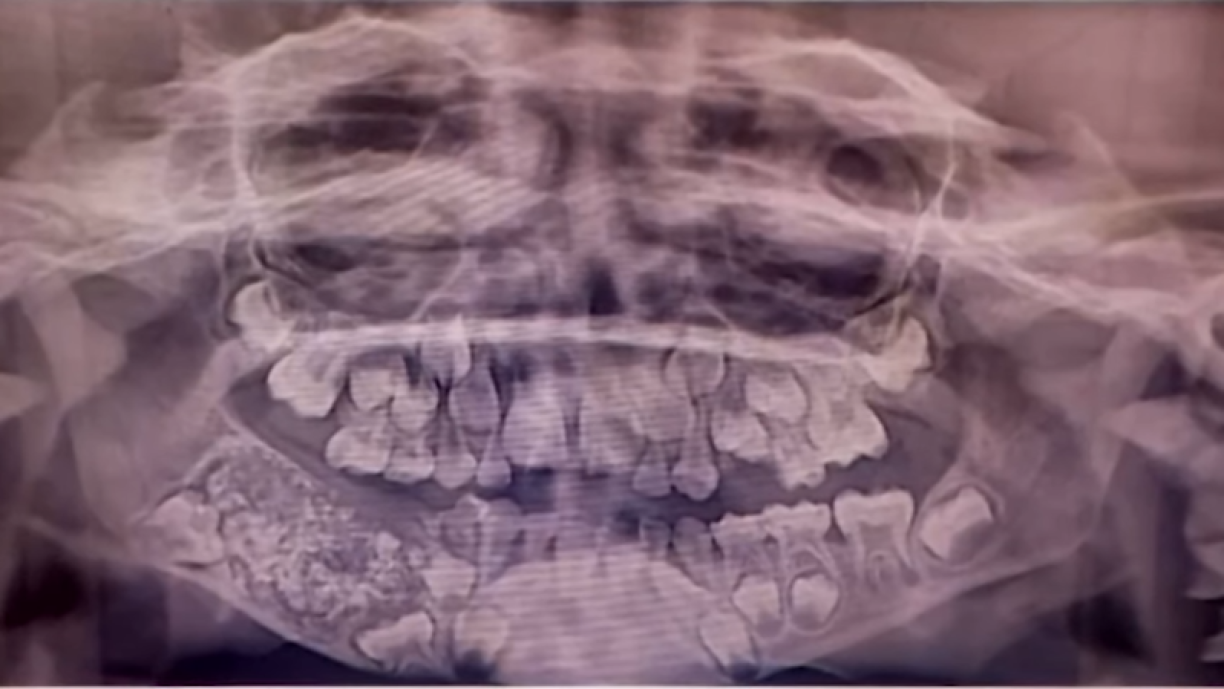

Eng ongewéinlech héich Zuel un Zänn hat ee 7 Joer ale Jong an Indien a sengem Mond. Bei enger Operatioun, déi 5 Stonne laang gedauert huet, hunn Dokteren an der Klinik Saveetha Dental College and Hospital zu Chennai 526 Zänn mat enger Gréisst tëscht 0,1 Millimeter a 15 Millimeter erausgeholl.

De Jong aus dem Südoste vun Indien hat virdrun iwwer Wéi am Kifer geklot an dëse war och geschwollen.